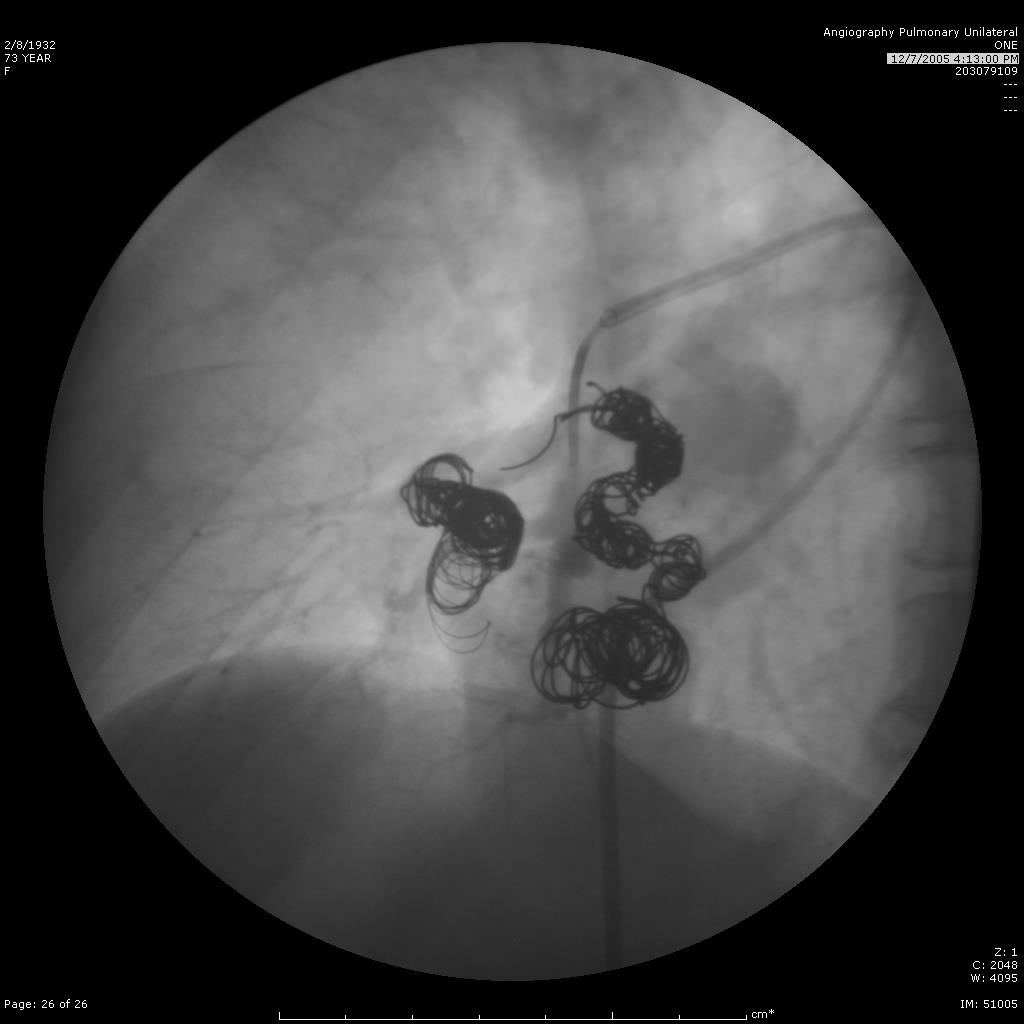

继续栓塞 |

|

研究静脉池出口情况 |

寻找最佳工作位 |

静脉池出口直径大 |

静脉池出口直径大 |

放弃静脉池栓塞,仅栓塞滋养动脉 |

完成任务 |